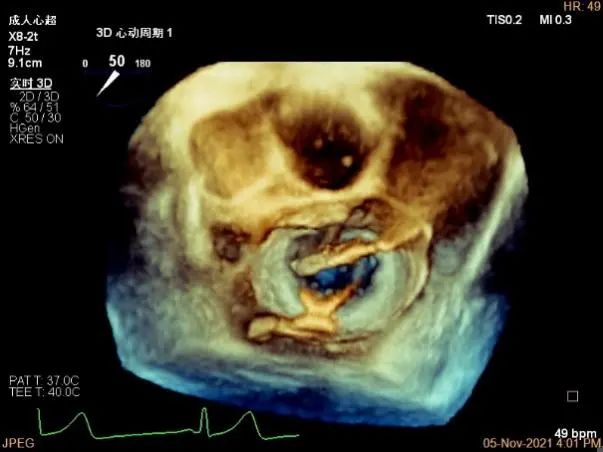

3D视图下进夹子并建立trajectory

3D视图打开夹子

3D视图下调Rotate,主要定位2区

夹子逐渐夹闭后,返流量逐渐减少

夹子放置后二尖瓣口平均跨瓣压差:1mmHg

肺静脉血流频谱恢复正向

夹子脱钩后,最终仅少量残余分流